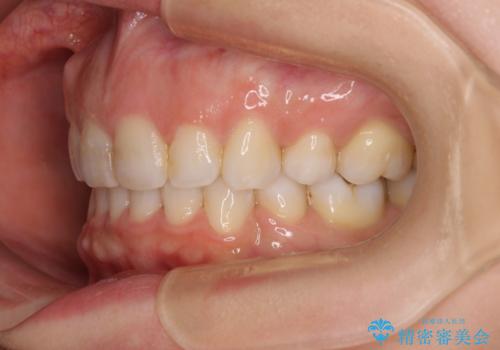

- 口元の閉じにくさと、奥歯の咬み合わせを気にして来院された患者様です。

左下の大臼歯2本が顕著に舌側に傾斜しているため、まずは奥歯の咬み合わせを改善をし、その後上下左右の第1小臼歯4本を抜歯することで口元を引っ込めながら整えることとしました。

奥歯の咬み合わせ改善には1年ほどの期間と処置中の噛みにくさを強いることとなりましたが、抜歯後はスムーズに治療を完了させることができました。

歯ぎしりの際に奥歯が干渉していた咬み合わせも理想的な状態に改善できました。